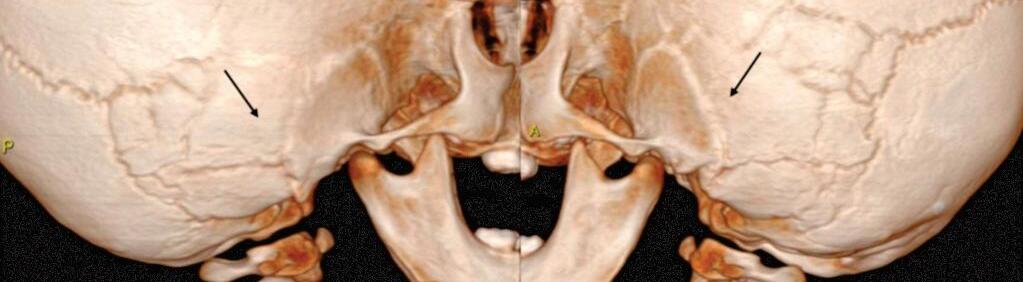

Fig. 1-7. (a, b) Histiocitose de células de Langerhans. Lesões osteolíticas frontal esquerda e nos ossos temporais. TC axial (a): axial: lesões focais osteolíticas bem definidas na porção escamosa dos ossos temporais, mais extensa à esquerda (setas).

1-8. Malformação da orelha externa. Microtia (seta em a), atresia do conduto auditivo externo (CAE), placa óssea atrésica (b).

1-9. Malformação das orelhas externas e média. Atresia óssea bilateral. (a) TC coronal bilateral: placas ósseas atrésicas (setas) e cavidades timpânicas rudimentares. (b) Reconstrução 3D de TC visão lateral: CAE não individualizados, placa óssea atrésica (setas).